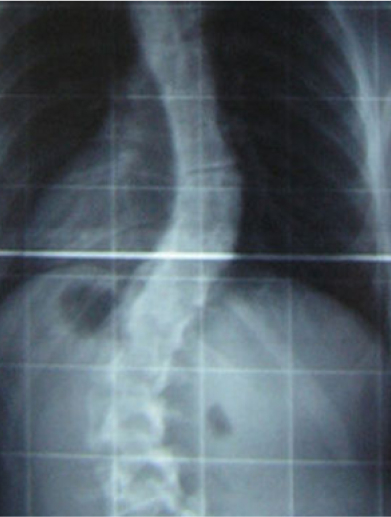

Scoliose is een driedimensionale zijdelingse verkromming en rotatie van de wervelkolom. Er kunnen één of meerdere bochten ontstaan in de rug. Tevens ontstaat een eenzijdige bolling van de ribben aan de achterkant; een gibbus.